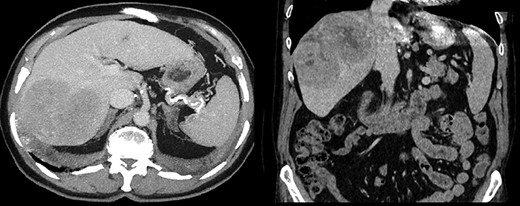

A 64-year-old male with severe ischemic cardiomyopathy underwent implantation of an LVAD (Heart mate II™, Abbott, Chicago, USA) in 2012. Decision of LVAD as destination therapy instead of heart transplantation was made due to history of hepatitis B infection, chronic kidney insufficiency and COPD. Patient remained in good condition with normal LVAD function. Further history included atrial fibrillation and pulmonary embolism. In 2019, hepatocellular carcinoma (HCC) was incidentally detected in the postero-lateral sector of the liver. Preoperative LiMax-Test [2] revealed good liver function (316 μ/kg/h), MELD XI Score was 15 without signs of portal hypertension. Staging revealed no distant metastases and confirmed local resectability (comp. Fig. 1).

(a and b) LVAD and driveline in preoperative and postoperative CT scan scout. (c) Relocated driveline during laparotomy, forceps in former driveline exit.